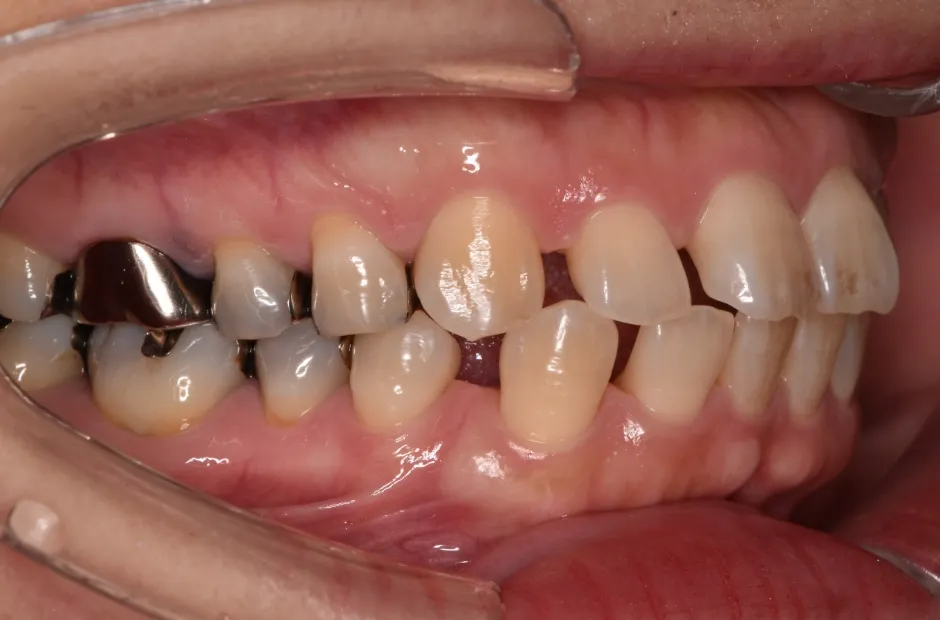

叢生

| 診断名・主訴 | 叢生 |

|---|---|

| 年齢・性別 | 43歳・女性 |

| 治療期間・回数 | 2年7か月 27回 |

| 治療に用いた主な装置 | 舌側矯正 |

| 抜歯部位 | 両顎4,4 |

| 治療費 | 100万円(税抜) |

| リスク・副作用 | 装置による違和感・疼痛・歯肉退縮・歯根吸収・虫歯のリスクなど |